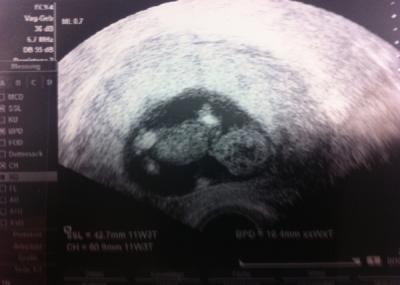

wollte euch gerne ein Bild zeigen, von gestern :)

danke :) nein aber hab es gesehen, hat man aber bei meinem kleinen schon ganz früh :) es hat sich so schön bewegt aber wollte sich nicht drehen, dass man mal Wirbelsäule und alles angucken kann. Aber ich war happy zusehen dass alles dran ist :) beide Beinchen, Zehen , Ärmchen und Fingerchen :) sogar die Ohren :)))